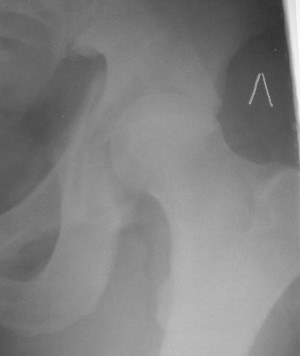

Контрольный снимок перед разрешением нагрузки прямой 13/10/03

Перед разрешением нагрузки боковой 13/10/03

Больной 18 мая 2003 года в автоаварии получил перелом левой вертлужной впадины, вывих бедра. Госпитализирован в один из стационаров области.Вывих вправлен. В последствии бедро вывихивалось еще дважды. На консультацию был представлен снимок от 19.05.03г., больной переведен к нам 3.06.03г. Снимок при поступлении - перелом впадины, задне-верхний вывих бедра. 05.06.2003 г. выполнено открытое вправление вывиха левого бедра и остеосинтез стенки вертлужной впадины двумя винтами. Послеоперационный период без осложнений. Объем движений в левом тазобедренном суставе восстановился полностью. Выписан на амбулаторное лечение в удовлетворительном состоянии с рекомендациями 3 месяца ходить на костылях без нагрузки на оперированную конечность. На контрольных рентгенограммах левого тазобедренного сустава 13.10.2003 г. - признаки консолидации перелома; плотность, форма головки и состояние суставных поверхностей удовлетворительные. Разрешена дозированная осевая нагрузка, на конечность с использованием дополнительной опоры. 19.12.2003 г. больной обратился с жалобами на боли в левом тазобедренном суставе. На рентгенограммах левого тазобедренного сустава 19.12.2003 г., 20.02.04г. - асептичекий некроз головки бедра. 5.04.04г. - эндопротез. Сейчас ходит без трости, не хромает. Особенность эндопротезирования - при удалении винтов прослежена линия перелома заднего края впадины и предложено установить чашку несколько меньшего диаметра, чтобы она была покрыта несломанной частью.